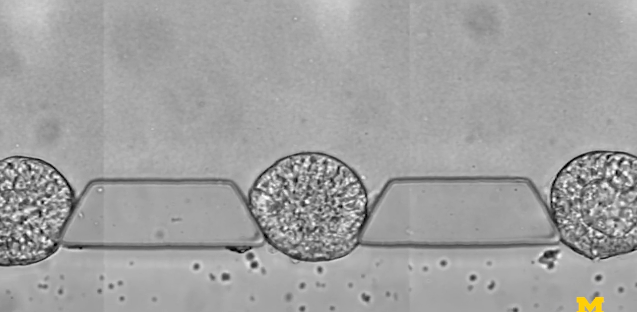

研究人員由此開發出來一種微流體裝置——由三個通道組成,分別用于放置細胞可嵌入的材料,裝載干細胞,以及輸運刺激干細胞分化的因子,借此研究人員能夠控制干細胞在早期人類胚胎中面向主要細胞譜系的分化,可以可靠地產生數百或數千種類似胚胎的結構。

圖 | 微流控芯片的特寫照片,該芯片幫助干細胞組織成胚胎樣結構,用于研究早期人類發育(來源:Fu Lab, Michigan Engineering)

為了模擬胚胎著床后的發育階段,即羊膜囊開始形成的時候,也是干細胞向分化成組織邁出第一步的時候,研究小組在一個可伸縮的三通道微流體系統中嘗試培育干細胞。中央通道包含一種模擬子宮壁的凝膠,兩側有一個通道用于為干細胞補充營養,另一個通道用于遞送引導。

圖 | 傅劍平實驗室研制的一套微流控裝置(來源:Fu Lab, Michigan Engineering)